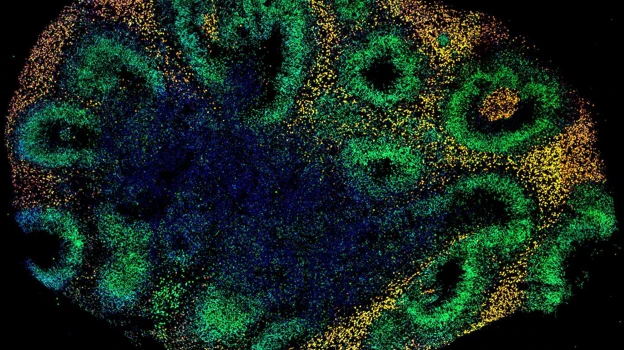

De estos últimos, entre toda la gama de los bautizados como organoides, los más llamativos son los cerebros. En realidad, minicerebros, un término polémico que si bien encaja en titulares sorprendentes, crea revuelo entre los científicos, que aún debaten cómo llamarlos. Explicados de manera sencilla: se trata de grupos de células que crecen en una placa de Petri, se agrupan y acaban funcionando de forma parecida a procesos que ocurren dentro de nuestras cabezas.

De momento, no son cerebros completos; pero sirven como modelos simplificados y en miniatura (miden apenas unos milímetros, con un aspecto parecido a un grano de arroz) con los que experimentar, y con los que ya se han conseguido logros que van desde minicerebros a los que les han crecido ‘ojos’ a implantes en la mente de ratones, lo que abre la puerta a toda una revolución científica.

«El objetivo no es crear Frankensteins», advierte a ABC Víctor Borrell Franco, investigador del Instituto de Neurociencias, centro mixto de titularidad mixta entre el Consejo Superior de Investigaciones Científicas y la Universidad Miguel Hernández (CSIC-UMH). Habla con conocimiento de causa: gracias a los minicerebros, su equipo ha descubierto un gen que provocó que, hace tres o cuatro millones de años, nuestra corteza cerebral, la parte más compleja y grande de nuestro cerebro, creciera, convirtiéndonos en humanos. El hallazgo fue publicado en la revista ‘Science Advances’.

Su campo, el desarrollo embrionario –el estudio cómo funcionan nuestras primerísimas células, cuando apenas medimos como un guisante–, está siendo uno de los más prolíficos en cuanto al uso de minicerebros. Entre la explosión de investigaciones, medios de todo el mundo se hicieron eco de unos minicerebros con ‘ojos’, unos ‘vistosos’ organoides creados para estudiar el origen de la vista.

Publicado en la revista ‘Cell Stem Cell’, el experimento consistía en hacer crecer organoides de copas ópticas –las estructuras desde las que se desarrolla casi todo el globo ocular– si bien con un pequeño añadido: junto con minicerebros. Al igual que los embriones humanos, a los 50 días de desarrollo, estos minicerebros mostraban ‘ojos’ claramente visibles.

No solo eso: estas copas ópticas contenían diferentes tipos de células de la retina, que se organizaban en redes neuronales que respondían a la luz, e incluso contenían lentes y tejido corneal. Además, las estructuras mostraron que la suerte de ‘retina’ de estos organoides se conectaba con el minicerebro.